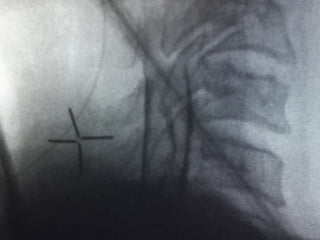

Epidural analgesia(failures)

Epidural analgesia

(failures)

Epidural failures (guess?)

Epidural failures

 Loss of resistance

Catheter placement

 Cervical – 1cm

 Thoracic-1.5 cm

 Lumbar – 2 cm

 Dermatomal involvement

 Calculation